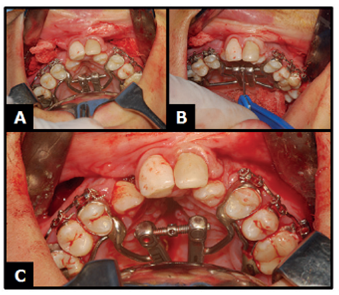

Posteriormente, deu-se início à osteotomia bilateral na região exposta (Figuras 2A, 2B e 3B, 3C, 3D). Ressalta-se que esse passo pode ser realizado tanto com serra quanto com broca número 702, sendo necessário prover um espaço ligeiramente maior no pilar zigomático a fim de que no momento da ativação do parafuso expansor não ocorra obstrução mecânica local.

A) Início da osteotomia com broca 702; B) Osteotomia finalizada do lado direito.

Figura 2: A) Início da osteotomia com broca 702; B) Osteotomia finalizada do lado direito.

Fonte: Documento obtido durante o estudo.

Em seguida, com o cinzel reto foi conferida a osteotomia desde o pilar zigomático, até as placas do pterigoideo -processos pterigoideos do osso esfenoide- em ambos os lados (Figuras 3A e 4A, 4B).

A) Cinzel reto para conferir a osteotomia; B) Hemostasia; C) Exposição do segmento posterior esquerdo; D) Osteotomia finalizada.

Figura 3: A) Cinzel reto para conferir a osteotomia; B) Hemostasia; C) Exposição do segmento posterior esquerdo; D) Osteotomia finalizada.